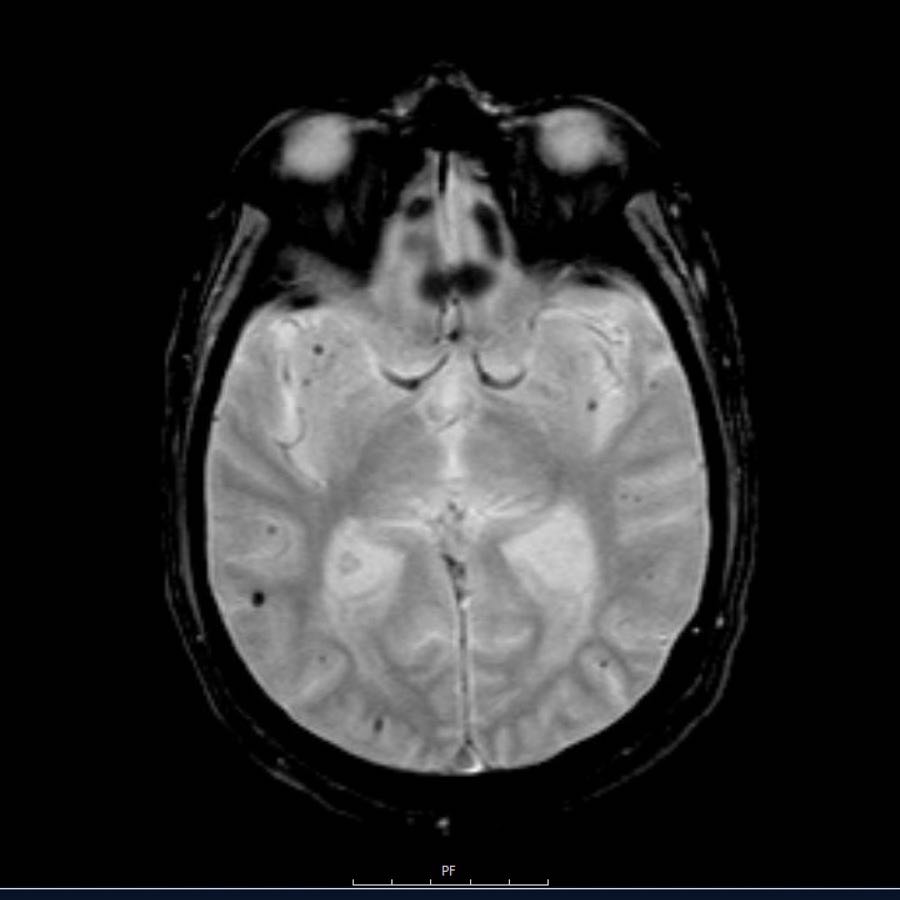

Bệnh nhân này nhập viện với xuất huyết tiểu não.

Các hình ảnh chuỗi xung gradient echo cho thấy nhiều vi xuất huyết.

Đây có thể là hậu quả của tăng huyết áp lâu năm do vị trí trung tâm của một số vi xuất huyết.